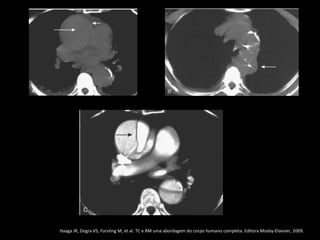

Haaga JR, Dogra VS, Forsting M, et al. TC e RM uma abordagem do corpo humano completa. Editora Mosby-Elsevier, 2009.

Pseudoaneurisma crônico

Trauma torácico: coice de um cavalo

História remota de acidente automotor